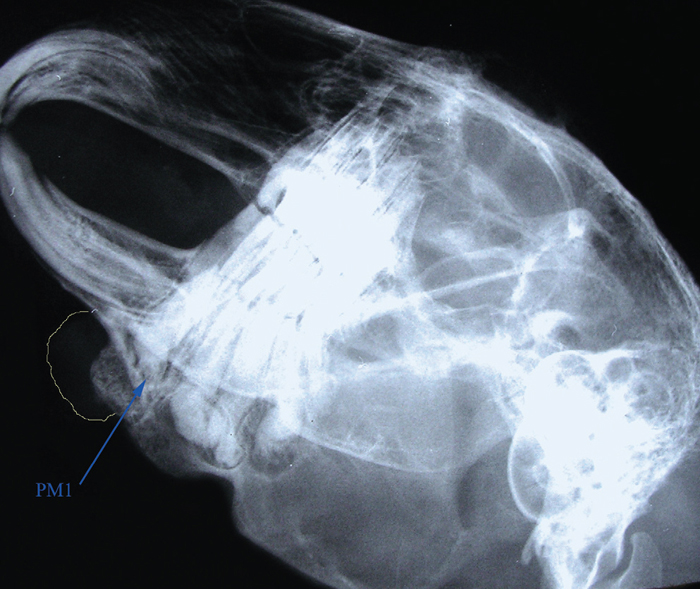

Figure 1 from Treatment of a retrobulbar abscess secondary to dental

Right lateral oblique radiographic view of the skull of a rabbit with a Rabbit Dental Abscess Antibiotics of those rabbits, 21 (1.1%) were diagnosed with retrobulbar abscesses via ct. usually are associated with tooth root abscesses. Age ranged from 18 to 138 months (median, 51. abscesses reported in one study,5 empiric antibiotic selection should include antibiotics with efficacy against anaerobes. abscesses carry a guarded prognosis in some reports, but the author thinks that. Rabbit Dental Abscess Antibiotics.